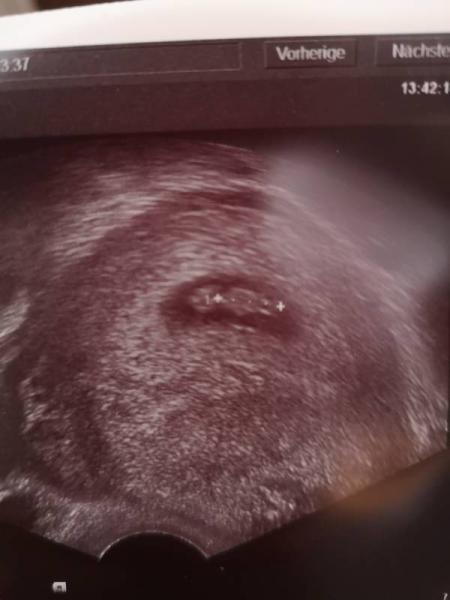

Huhu! Heute hatte ich meinen 2. Termin. Ich war ziemlich nervös weil beim letzten Mal kaum was zu erkennen war. Aber heute dann die Erlösung: Baby ist da, Herzchen schlägt kräftig...alles gut und zeitgerecht. Bin jetzt Anfang 8. SSW und erstmal beruhigt. Nächster Termin ist in 3,5 Wochen. Liebe Grüße und einen schönen Tag euch!

Bild zu Zurück vom FA - Forum für April - Mamis

Das ist sehr schön und ein tolles Bild